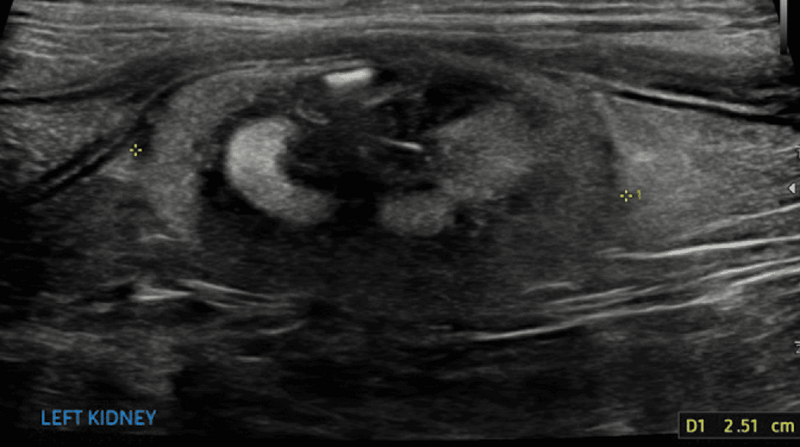

Poszerzenie miedniczki nerkowej (pielektazja)

Poza takimi czynnikami jak dożylna płynoterapia lub odmiedniczkowe zapalenie nerek zwiększone wydalanie moczu u pacjentów z przewlekłą chorobą nerek jest często związane z poszerzeniem miedniczki nerkowej.16 Pielektazja to nagromadzenie płynu i wtórne rozszerzenie miedniczki nerkowej wynikające z procesu niezwiązanego z niedrożnością (ryc. 8).8 Dla porównania wodonercze to rozszerzenie miedniczki nerkowej wtórne do niedrożności dróg moczowych. Pielektazja jest najczęściej symetryczna i obustronna, może jednak występować jednostronnie lub asymetrycznie w obu nerkach.3,16 U pacjentów z pielektazją i niewydolnością nerek wysokość miedniczki nerkowej zazwyczaj nie przekracza 3,4 mm u psów i 3 mm u kotów.16 Jeżeli poszerzenie miedniczki nerkowej jest większe, należy dokładnie ocenić drogi moczowe pod kątem nieprawidłowości, aby potwierdzić obecność innych procesów chorobowych, takich jak odmiedniczkowe zapalenie nerek lub wodonercze wtórne do niedrożności dróg moczowych.16

Medium huguet ryc8 opt

Ryc. 8. Obraz w projekcji poprzecznej prawej nerki psa, ukazujący łagodne poszerzenie miedniczki nerkowej (wysokość miedniczki nerkowej oznaczona wskaźnikami). Brak cech niedrożności.